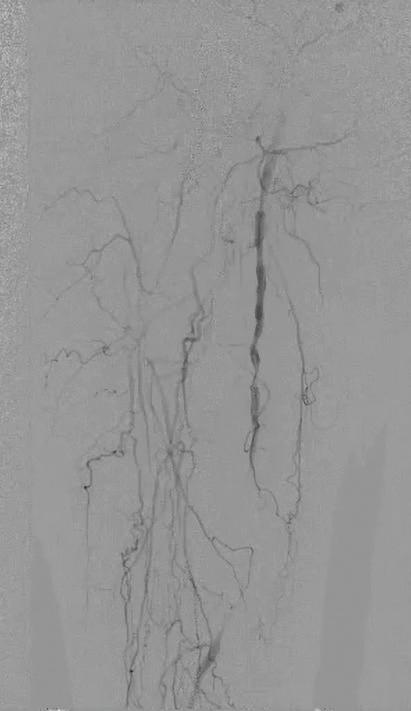

*All: drug, scaffold, resorbable excluding platinum markers.

1. Reintervention defined as CD-TLR. 2. Brian G. DeRubertis et al., Two-Year Outcomes of the LIFE-BTK Randomized Controlled Trial Evaluating the Esprit™ BTK Drug-eluting Resorbable Scaffold for Treatment of Infrapopliteal Lesions, VIVA 2024.

INDICATIONS The Esprit™ BTK Everolimus Eluting Resorbable Scaffold System is indicated for improving luminal diameter in infrapopliteal lesions in patients with chronic limb-threatening ischemia (CLTI) and total scaffolding length up to 170 mm with a reference vessel diameter of ≥ 2.5 mm and ≤ 4.00 mm.

MAT-2408411 v3.0 48% fewer patients require reinterventions through 2 years.1,2 Go above expectations with the only device that does it all for CLTI.*